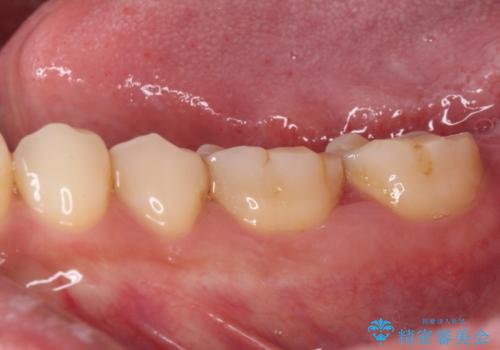

奥歯の歯間部の歯肉が炎症で赤黒くなっており、歯周ポケットを検査したところ、6-8mm(正常では3mm以下)であり、外科処置が適用となる状態でした。

まずは仮歯に置き換え、歯周ポケットを除去するための外科処置(歯肉弁根尖側移動術)を行い、治癒を待ってセラミッククラウンにて補綴治療を行うこととしました。

外科処置後は知覚過敏症状が酷くなることが多いのですが、術後は比較的落ち着いており、スムーズに処置を進めることができました。